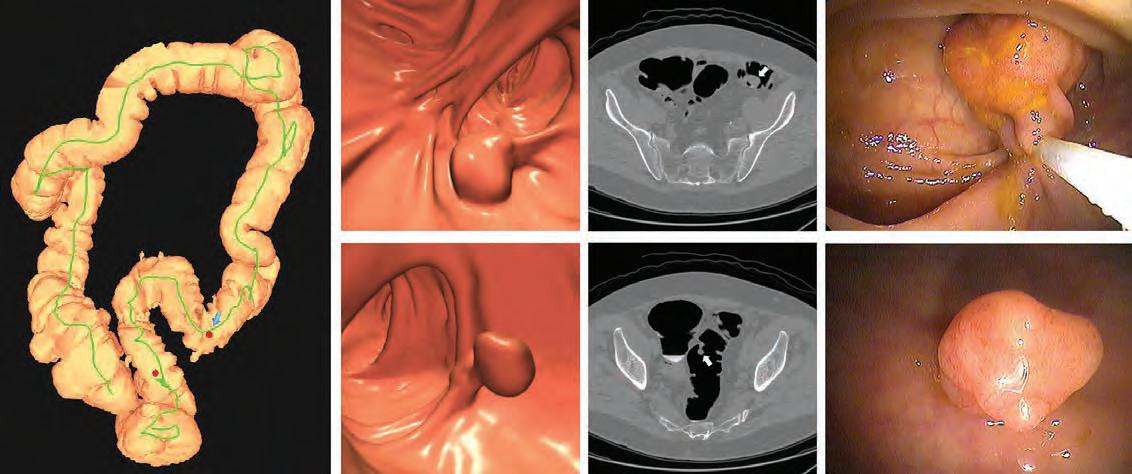

Despite being preventable, colorectal cancer (CRC) is one of the leading causes of cancer deaths in the United States. Colonoscopy has been the predominant option for screening and identifying precancerous polyps, but multitarget stool DNA (mt-sDNA) has gained popularity in recent years due to its non-invasive nature. At UW Health, another non-invasive option, CT Colonography (CTC), is available; and according to data from a 20-year-long program led by Perry Pickhardt, MD and David Kim, MD, it may be the best option for many patients.

Unlike colonoscopy, there’s no risk of bleeding or perforating the colon associated with CTC. Instead of a scope, computed tomography scans are used to create 3D images of a patient’s colon from different angles. Patients are able to resume normal activities and even drive themselves home following the procedure. If polyps are detected, same-day GI Clinic services are available for polypectomies.

While stool testing is also a non-invasive screening method, CTC outperforms it in a crucial area: detecting precancerous polyps. By identifying and removing these types of polyps, patients can effectively prevent cancer that they may have developed later in life.

Images of positive CT colonography (CTC) screening examination result in an asymptomatic patient. Colon map from CTC (left image) shows the location of two sigmoid polyps that were detected (red dots). Three-dimensional endoluminal and confirmatory two-dimensional transverse CTC images show a large 1.6-cm pedunculated polyp on top row (arrow) and a 9-mm pedunculated polyp in the distal sigmoid on the bottom row (arrow). Both polyps were confirmed and resected at optical colonoscopy performed the same day (right images), avoiding the need for a second bowel preparation. The larger polyp proved to be a tubulovillous adenoma (large advanced adenoma), whereas the smaller polyp was a nonadvanced tubular adenoma.